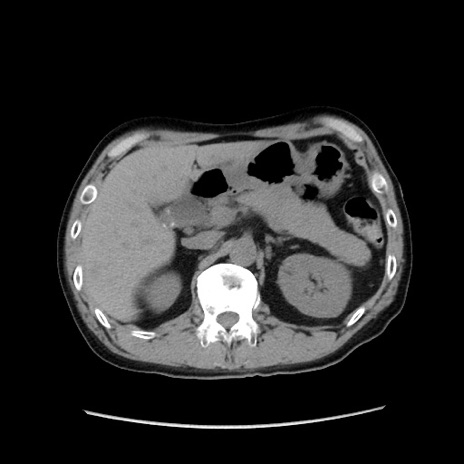

症例37(横断像)

【症例】40歳代 男性

【主訴】腹痛

【現病歴】4時間ほど前に電車に乗車中に臍部上より腹痛出現。徐々に増悪し起立困難となり、救急外来受診。生ものは数日食べていない。今朝お雑煮を食べた。

【身体所見】BT 36.8℃、BP 117/84mmHg、HR 91/min、SpO2 97%、苦悶様、腹部:臍上部広範囲圧痛あり、反跳痛±

【データ】WBC 8100、CRP 0.03